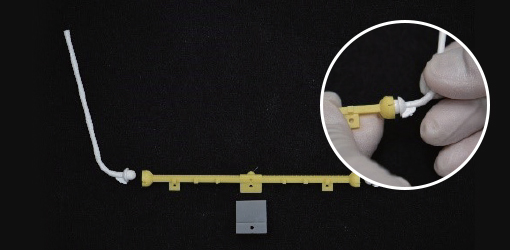

1. Prepare the POP stick and POP arm by connecting them to one another

1. Prepare the POP stick and POP arm by connecting them to one another